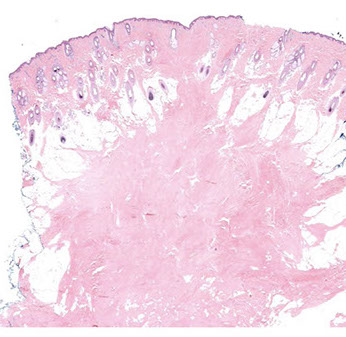

Angiofibroma

- aka fibrous papule

Common, b9, small, reddish brown of flesh-colored smooth shiny papules over the sides of the nose and the medial portion of the cheeks

Multiple angiofibromas can be seen in NF, Birt-Hogg-Dube, MEN1 or TS (esp if multiple, reddish brown lesions on face in younger pts, which are called adenoma sebaceum [a total misnomer bc they are really angiofibromas])

Micro: dark pink dense collagenous stroma c inc spindled to stellate fibroblasts and inc and dilated BVs

- collagenous stroma consists of collagenous alteration c concentric orientation around hair follicles or BVs or perpendicular to epidermis

- stellate or triangular dark "Star Trek cells" are fibroblasts in dense, fibrotic collagenous stroma

- multinucleated fibroblasts often present, scattered dermal melanophages may be seen

- rare mits

Many histologic variants: Hypercellular, clear cell, pigmented, pleomorphic, granular

IHC: not usually necessary, but may help r/o malignancy; spindled and stellate cells (+) for FXIIIa, CD68 and CD34 and neg for CKs and S100

DDx: Angiofibromas of TS (adenoma sebaceum), angioma (angioma does not have as thick colalgen or stellate / triangular cells), fibrofolliculoma, pleomorphic fibroma

Angiofibroma with dense pink collagen, dilated BVs, and dark "Star Trek" fibroblasts